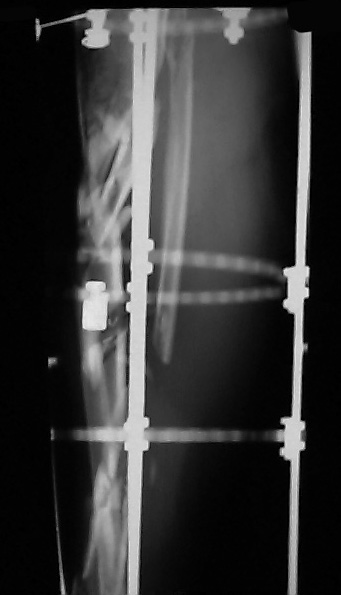

I would appreciate treatment suggestions.My patient is a 30 year old with a very comminuted tibia fracture 6 weeks ago.It was grade 3B open. Initial treatment included irrigation, debridementClick images to enlarge.

and a hybrid external fixator including femur, tibia and foot. Screwswere placed in the plateau and plafond and a free flap plus STSG. Theskin is ok but atrophic. The femoral pins were removed and knee motionstarted at 6 weeks. There is no sign of callus. There is one pin inthe one large fragment of the diaphysis. All the pieces are lined upreasonably well. The XF pins are ok. Suggestions? Thank you.